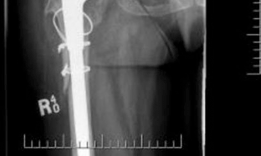

A highly porous metal cup is then impacted into the defect. The cup is often placed in an off-axis orientation, prioritizing host bone contact and initial stability over anatomic version and inclination. The subsequent cementation of the liner into the cage will correct the final articular geometry. If large cavitary defects remain behind the cup, highly porous metal augments or impacted cancellous allograft are utilized to fill the voids and support the primary shell. Multiple multi-hole screws are placed through the cup into the superior dome and posterior column to maximize initial fixation.

Cage Contouring and Fixation

The appropriate cage is selected based on preoperative templating and intraoperative trialing. The inferior flange is contoured to fit into the prepared ischial slot. The superior flange is contoured to lie flush against the lateral aspect of the ilium. Proper contouring is critical; a poorly contoured cage will experience high bending moments and subsequent fatigue failure.

The cage is inserted by first seating the inferior flange into the ischium. The superior flange is then impacted against the ilium. The cage should sit intimately against the previously placed highly porous cup. Fixation begins with the placement of cortical or cancellous screws through the superior flange into the dense bone of the ilium, aiming toward the sacroiliac joint. Screws are also placed through the central dome of the cage, passing through the cage, the underlying porous cup, and into the host bone, effectively locking the two components together. Care must be taken to avoid the superior gluteal neurovascular bundle during superior flange screw placement and the external iliac vessels during anterior screw placement.